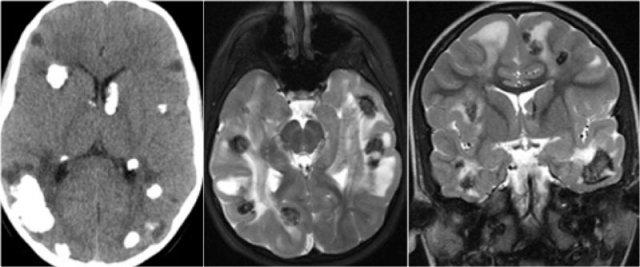

Chuỗi xung T2W và T2* gradient echo cho thấy nhiều cavernoma.

Lưu ý hình ảnh “bỏng ngô” với vành hemosiderin ngoại vi trên chuỗi xung T2W.

Các tổn thương gần như hoàn toàn màu đen trên chuỗi xung gradient echo do xảo ảnh blooming.

Chuỗi xung T2* và hình ảnh trọng số độ nhạy từ (SWI) làm tăng đáng kể độ nhạy của MRI trong việc phát hiện các cavernoma nhỏ.

Năm chấm đen ở bán cầu đại não trái trên chuỗi xung T2* cũng là cavernoma và không thể nhìn thấy trên chuỗi xung T2W.